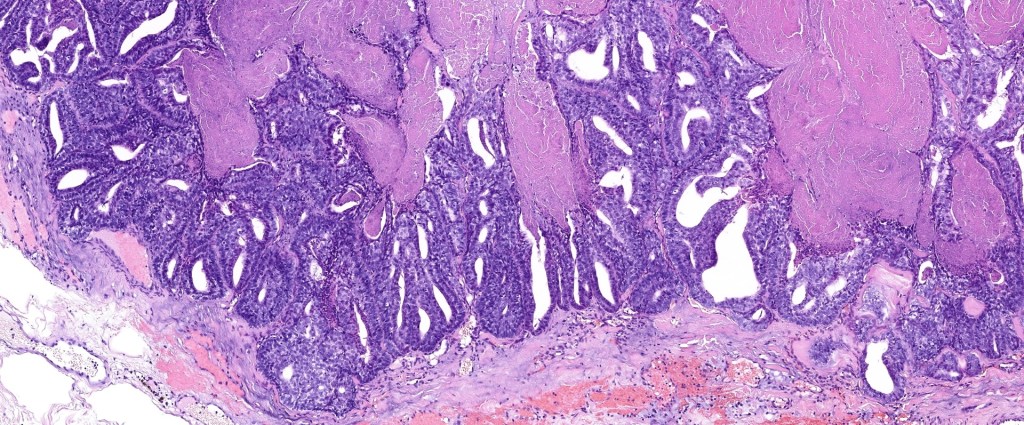

•Papillary component (may include pseuopapillae & true papillae with a fibrovascular core)

•Back-to-back glands with double-layered epithelium

•Cuboidal/columnar with eosinophilic cytoplasm & vesicular nuclei

•Often dense, hyalinized collagenous stroma